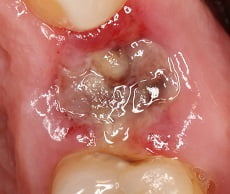

Альвеолит: фото

Фото, сделанные стоматологами, демонстрируют, что альвеолит выглядит как пустая лунка, в которой находятся остатки пищи и частички отмерших тканей. В то время как в лунке, заживающей без осложнений, можно увидеть темно-красный кровяной сгусток.